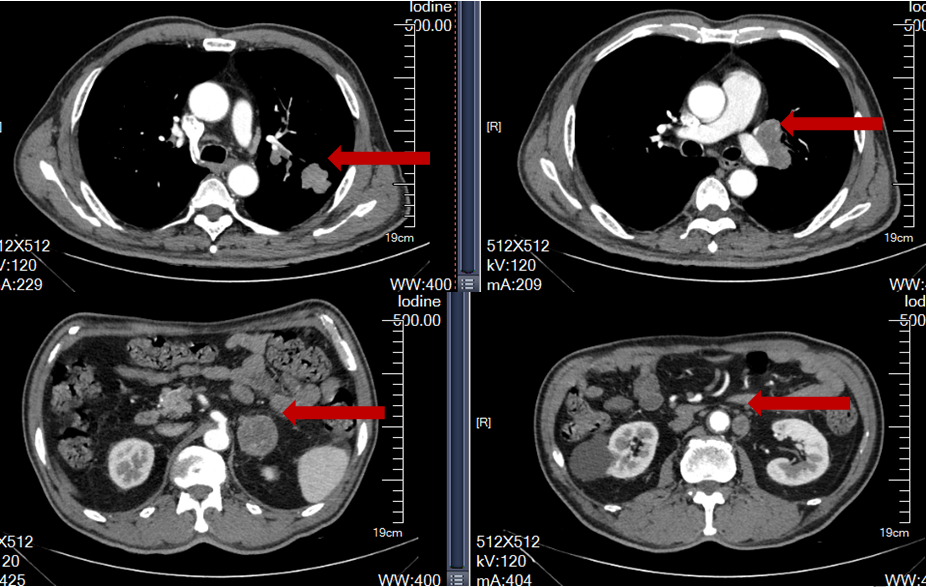

2022-08-08胸腹盆腔CT:1、左肺上叶占位并左肺门多发肿大淋巴结,考虑肺Ca并淋巴结转移,建议穿刺活检;双侧肾上腺占位,考虑转移瘤;腹膜后淋巴结转移2、双肺上叶磨玻璃小结节,较前变化不著;原左肺下叶实性小结节,现未见明确显示3、双肺肺气肿,多发肺大泡;双肺下叶少许炎症;左肺下叶钙化灶4、主动脉壁及冠状动脉壁钙化斑块5、右侧第5肋低密度影,建议随诊复查。

图2.首诊胸腹部CT